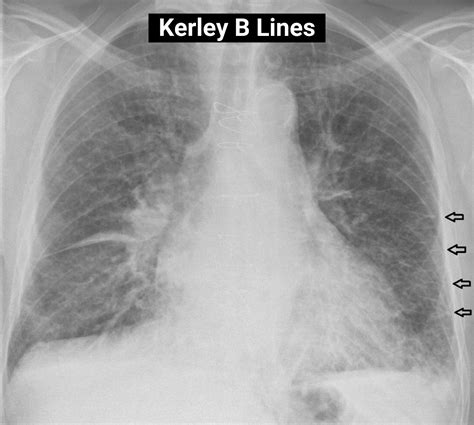

Discover what Kerley B lines reveal about your health. This guide explains these interstitial opacities, their connection to congestive heart failure, pulmonary edema, and pleural effusions. Learn how radiologists identify these chest X-ray findings to diagnose underlying cardiogenic conditions effectively. Gain essential insights into lung markings and clinical imaging interpretation for better understanding of this common diagnostic marker.